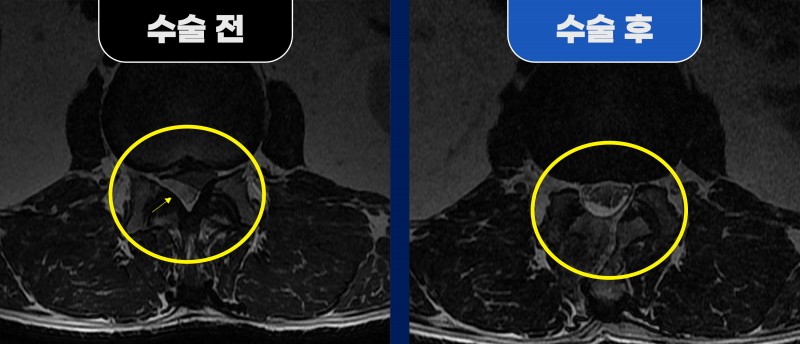

양하지 방사통·배뇨장애 동반한 드문 디스크 파열, 척추내시경으로 해결

55세 남자 환자분께서 양하지 방사통, 근력 저하, 배뇨장애를 주증상으로 내원하셨습니다.

MRI 검사에서는 요추 1/2번에서 신경을 압박하는 병변이 확인되었습니다.

수술 소견에서는 단순 협착이 아니라

파열된 디스크 조각이 신경 위까지 올라타며 압박을 일으킨 것으로 확인되었습니다.

■ After (수술 후)

척추내시경을 이용해 신경을 압박하던 파열된 디스크를 안전하게 제거하고,

동시에 반대측 신경관까지 충분히 넓혀주는 감압술을 시행하였습니다.

수술 후 환자분의 방사통과 신경증상은 대부분 호전되었으며,

빠른 회복을 보여 수술 후 3일 만에 퇴원하실 수 있었습니다.